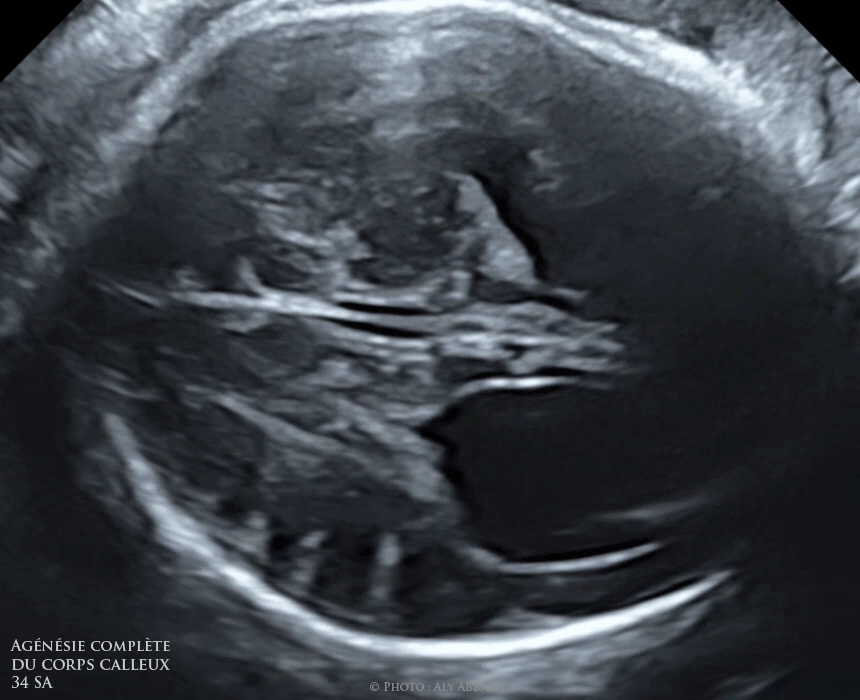

Agénésie du corps calleux description anatomique signes échographiques in utero

Agénésie complète du corps calleux Le signe de triple feuillet

Agénésie complète du corps calleux Colpocéphalie

Agénésie complète du corps calleux